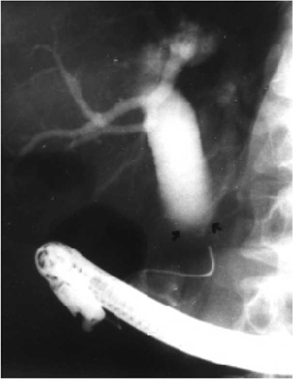

- PTC (Percutaneous transhepatic cholangiogram) – נראה חסימה בדרכי המרה ואת הגובה שלה בצינור המרה (תצלום 50.8).